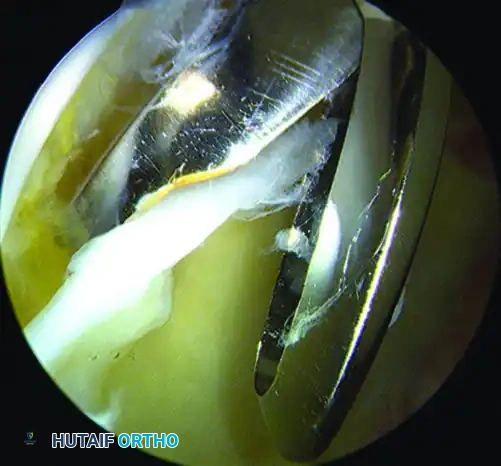

3. Central Compartment Arthroscopy

Once portals are established, an interportal capsulotomy is performed parallel to the acetabular rim to allow instrument maneuverability. The central compartment is systematically inspected.

Figure: Arthroscopic view demonstrating articular cartilage sheared from the subchondral bone of the acetabulum, a classic finding in cam impingement.

Figure: Arthroscopic view of a complex labral tear.

Pincer Resection and Labral Repair:

If a pincer lesion is present, the labrum is carefully detached from the overhanging bone. A motorized burr is used to perform an acetabular rim trimming, resecting the bony overcoverage until a normal center-edge angle is achieved. Following rim resection, the subchondral bone is decorticated to a bleeding bed. Suture anchors are placed precisely on the acetabular rim, and the labrum is refixed using looped or mattress suture configurations to restore the critical suction seal of the joint.